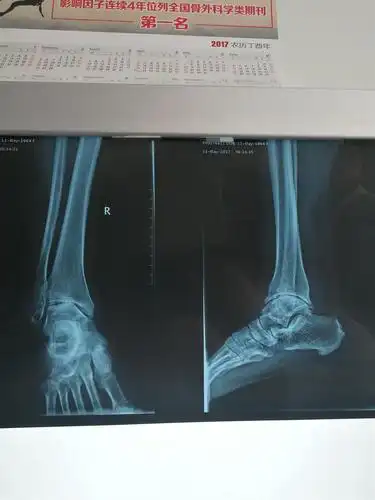

甘肃省人民医院骨一科杨青山副主任医师团队:踝关节骨折

矢状面:外踝较内踝偏向后1cm,后踝较前踝更向下延伸,限制距骨后移

踝关节侧位x线片